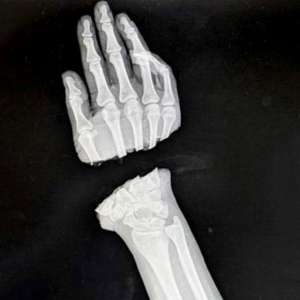

Врачи из Национального медицинского исследовательского центра травматологии и ортопедии имени Р. Р. Вредена совершили настоящий подвиг, спасши руку молодой девушке, которую во время работы на станке буквально отрезало.

28-летняя пациентка потеряла кисть, но благодаря усилиям врачей Артёма Афанасьева и Александра Чижова, которые провели семь часов за операционным столом, её рука была собрана буквально по кусочкам. Под микроскопом они соединили вены, артерии, сухожилия и нервы, вернув девушке способность двигаться и жить полноценной жизнью.

Конечно, после такого серьёзного хирургического вмешательства не избежать некоторых последствий, но в целом пациентка будет жить полноценной жизнью, имея две руки.

Мы желаем ей скорейшего выздоровления и выражаем огромную благодарность врачам Национального медицинского исследовательского центра травматологии и ортопедии имени Р. Р. Вредена за их профессионализм и преданность делу.